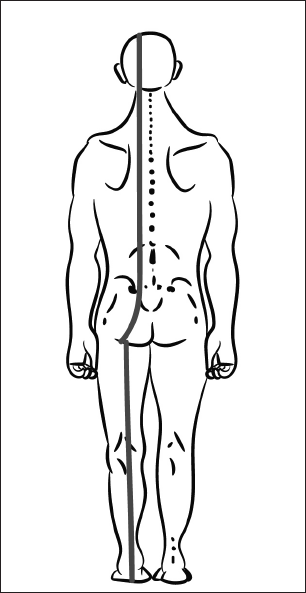

У взрослого человека он постепенно переходит в рефлекс поддержания головы в вертикальном положении, а мышцы-разгибатели формируют заднюю МФЦ (рис. 19).

Рис. 19. Задняя миофасциальная цепь.

Эта цепь позволяет поддерживать тело в вертикальном положении в статике и при ходьбе. Сокращаясь одномоментно, мышцы с одного конца цепи поддерживают баланс мышечной силы на другом.

С последующим развитием нервной системы задняя МФЦ вытягивается и начинается от подошвенной поверхности пальцев стопы.

Если пальцы стоп в ходьбе не участвуют, то сложная координационная мышечная цепь рассыпается на отдельные участки, вызывая избыточное сокращение в отдельных регионах позвоночника и конечностей.

Так возникает нарушение осанки в виде верхне-перекрещенного, нижне-перекрещенного и слоистого синдромов и нестабильность нескольких регионов – в динамике (рис. 20).